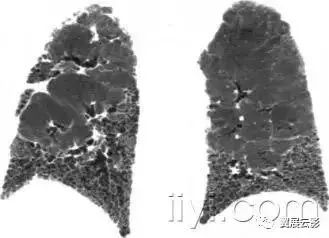

二十五、蜂窝征

病理:蜂窝征代表肺组织的破坏和纤维化,包括大量的囊样含气腔隙和厚纤维壁,是各种肺疾病的晚期改变,已经完全失去了腺泡的解剖结构。囊肿的直径大小从数个毫米到数个厘米,囊壁厚度不一,覆盖以化生的细支气管上皮。

平片和CT:在胸片上,蜂窝征表现为相邻很近的环状阴影,直径主要在3-10mm,壁厚主要在1-3mm,形似蜂窝。这一发现提示肺疾患的终末期。在CT上表现为成簇的囊样含气间隙,其直径大约在3-10mm,偶有大于62.5px的。蜂窝征通常见于胸膜下,具有清晰的壁是其特征,是肺纤维化的CT特征。因为蜂窝征常作为肺纤维化的特异性指标,是常见性间质性肺炎的诊断依据。应当慎用本术语,他可能对病人的治疗产生直接影响。